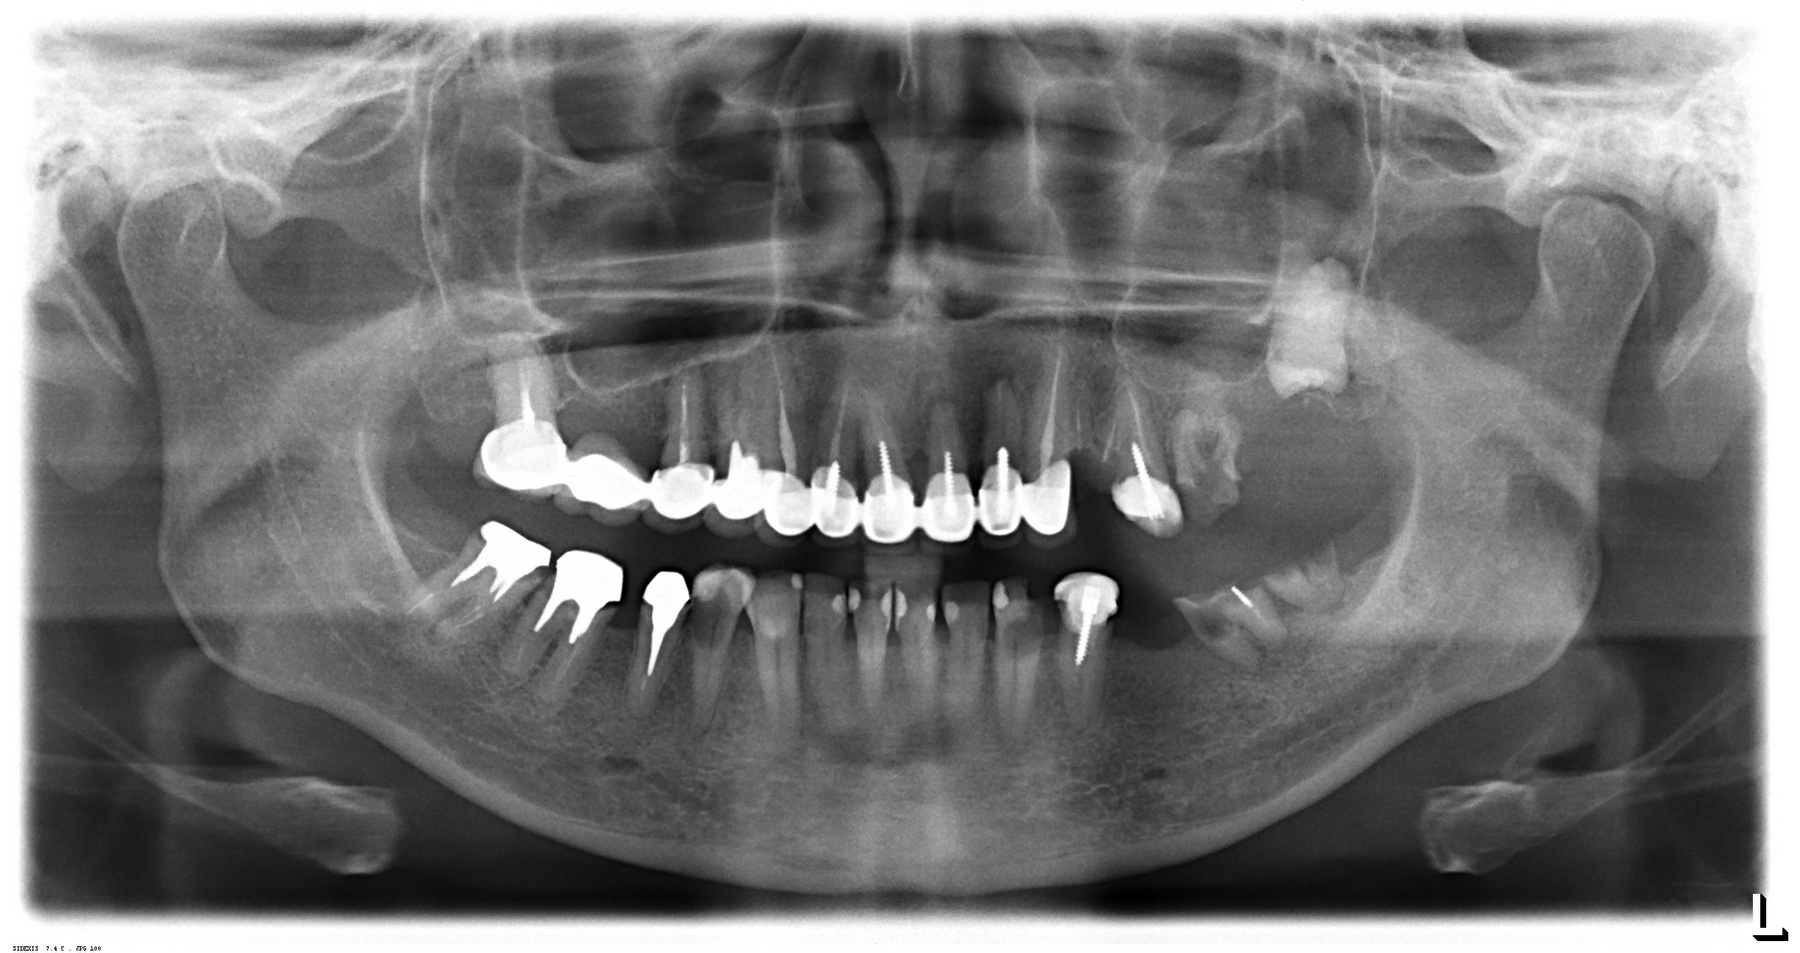

в ходе второго этапа было установлено три импланта в боковом сегменте верхней челюсти, удален ретинированный зуб мудрости, проведен синуслифтинг

Вторая операция заняла чуть больше времени (90 минут), поскольку потребовалось удаление ретинированного зуба мудрости и синуслифтинг. Послеоперационные явления более выраженные — отек держался в течение нескольких дней, болезненных ощущений почти не было.

Стоит ли сейчас приступать к третьему и четвертому этапам, а именно — к удалению зубов и имплантации на правой стороне? На мой взгляд, нет. И тут срабатывает принцип, поспешишь — людей насмешишь. Ну подумайте сами — у пациентки не интегрированы импланты с левой стороны, вся жевательная нагрузка приходится на правую сторону. Удалив зубы, мы сильно увеличим нагрузку на оставшиеся передние сегменты, которые, если честно, находятся не в лучшем состоянии. И это не говоря о том, как пациентка будет себя чувствовать, не имея возможности нормально пережевывать пищу. Поэтому в наших интересах — дождаться интеграции имплантов слева, установить на них временные протезы, перенести на них жевательную нагрузку, и только потом приступать к работе на правой стороне.